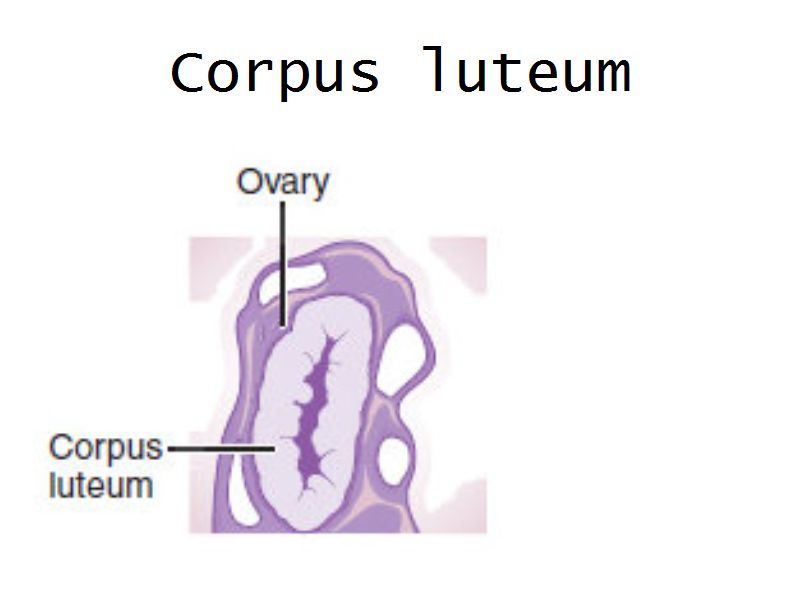

Corpus luteum

Slide 91

Corpus luteum

- Two major cell types

- Granulosa lutein cells

- modified granulosa cells

- Theca lutein cells

- modified theca interna cells

- Many capillaries